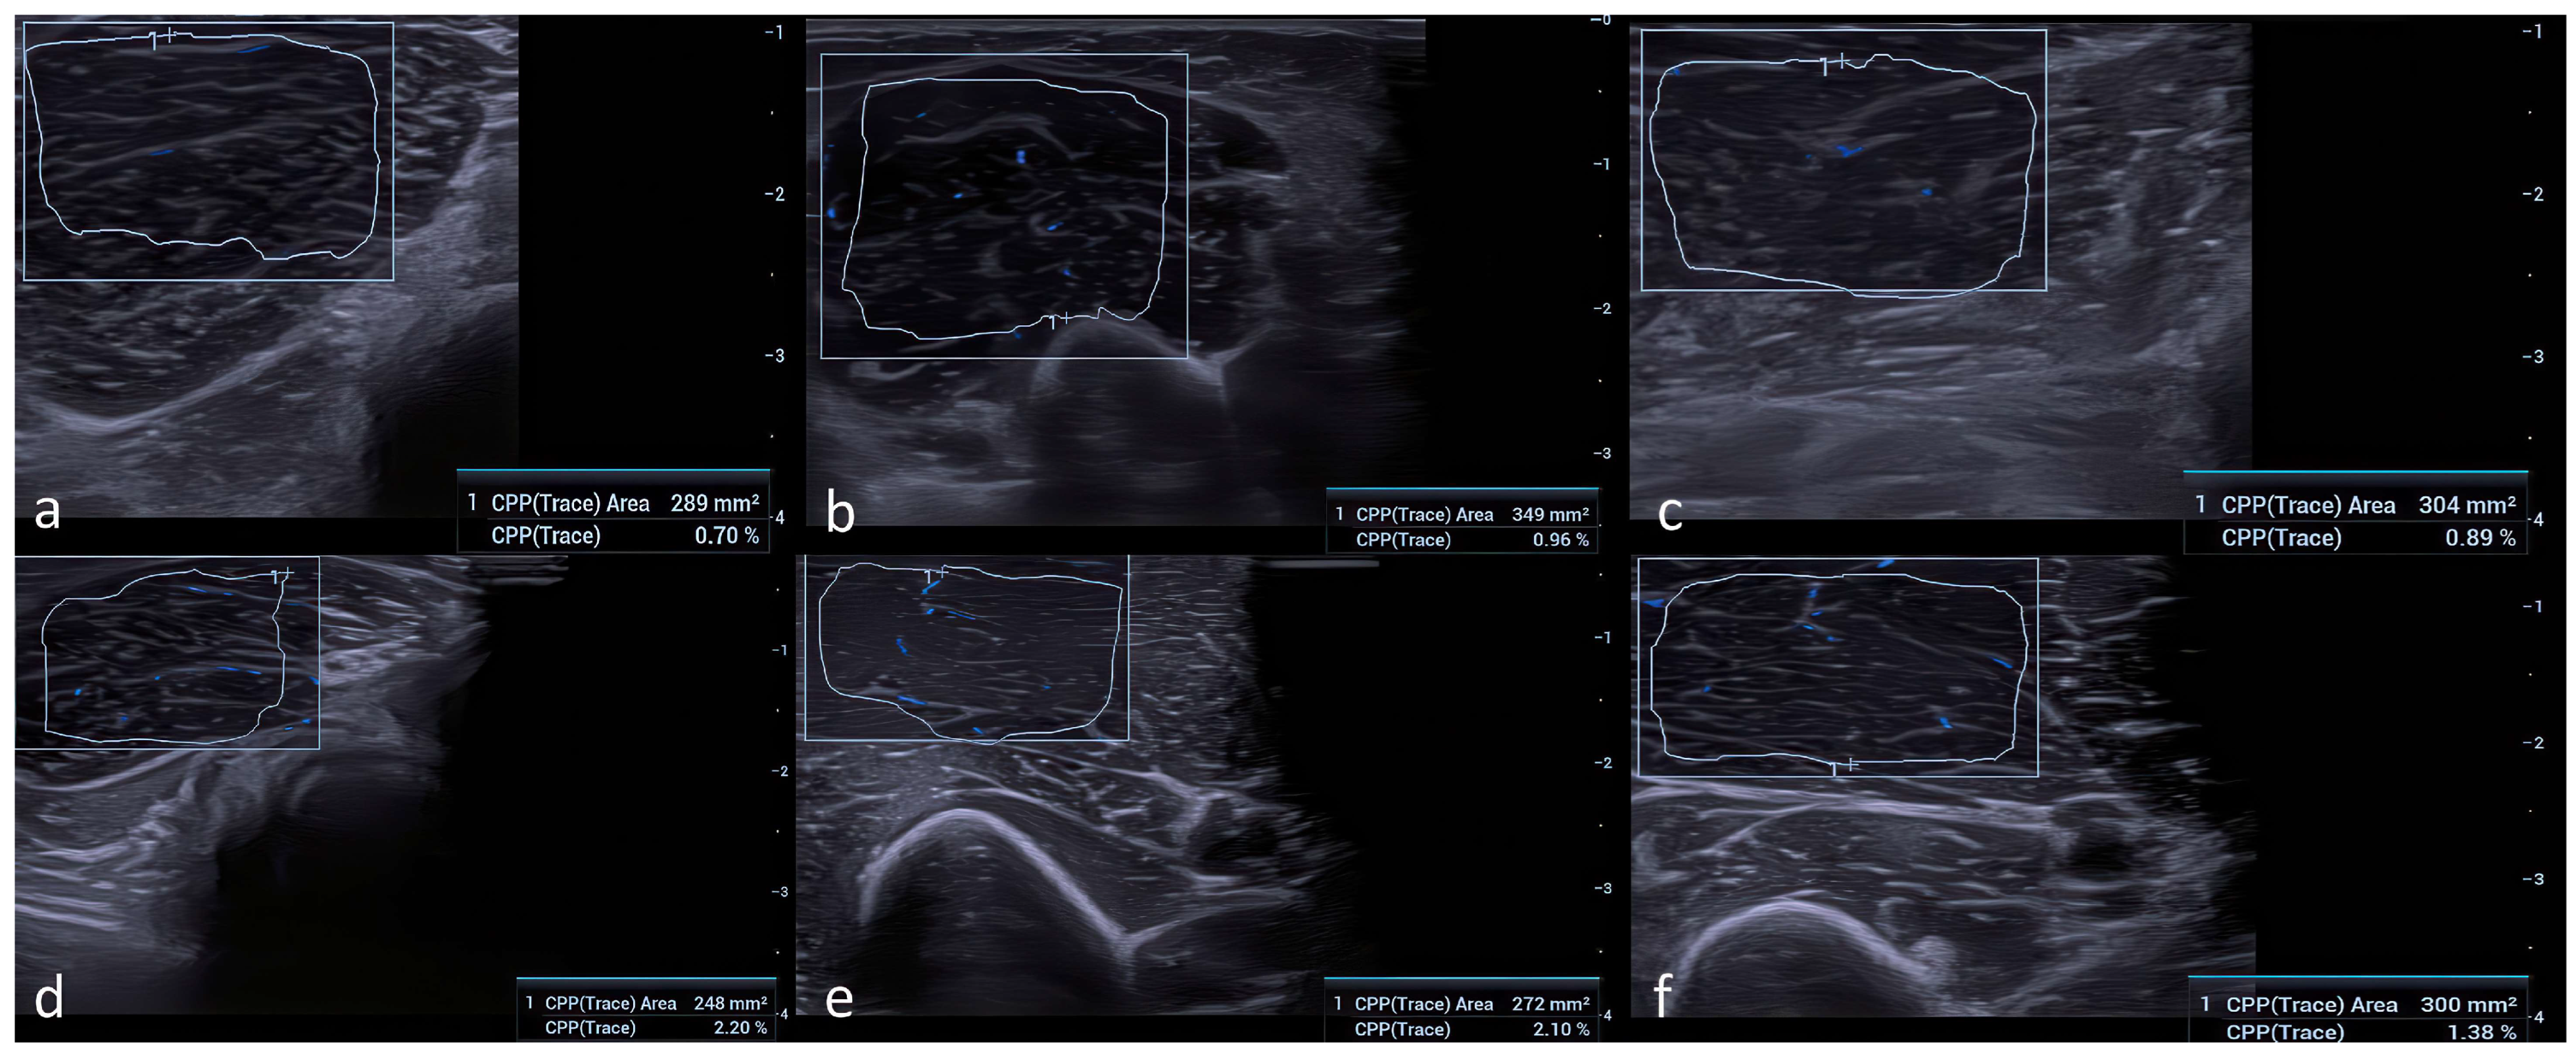

All volunteers included in the study were examined by two independent radiologists (with 9 and 18 years of professional experience, respectively), blinded to the participants’ medical history, surgical information, and clinical variables. Participants were recruited using a consecutive sampling approach from individuals referred for routine ultrasound examinations who met the inclusion criteria. Participants were instructed to avoid strenuous activity for at least 24 h prior to imaging, and examinations were performed with the muscles in a relaxed position at room temperature (22–24 °C). Grayscale ultrasound and Ultra-Micro-Angiography (UMA) examinations were performed using a high-frequency (14 MHz) linear array transducer (Mindray Resona I9, Mindray Medical Systems, Shenzhen, China). Imaging was conducted on the dominant extremities of the participants in the supine normoanatomic position, and participants were instructed to remain still to minimize motion artifacts. Copious coupling gel was applied to reduce subcutaneous tissue-related variability. The transducer was positioned perpendicular to the thickest mid-portion of the flexor carpi radialis (FCR), biceps brachii short head (BB), and tibialis anterior (TA) muscles. Cross-sectional area (CSA) measurements and vascular index (VI) values were obtained at these standardized locations using UMA (Figure 1). The vascular index (VI) was calculated as the ratio of color pixels to the total number of pixels within the selected region of interest (ROI), expressed as a percentage (VI = [color pixels/total pixels] × 100). To avoid artifacts, the ultrasound probe was held steady for 3–5 s, and VI values were recorded once UMA images stabilized. All grayscale ultrasound and UMA parameters were standardized and kept identical for all participants. UMA settings—including pulse repetition frequency (PRF), gain, frame rate, and wall filter thresholds—were held constant throughout the examinations. PRF was set at 600–800 Hz, the wall filter was set to the lowest available level, and gain was optimized to avoid blooming artifacts, ensuring that VI measurements reflected true microvascular signals rather than noise. In practice, PRF was initially set at the lowest level allowing stable signal detection and was minimally adjusted when necessary to avoid motion artifacts; all final PRF values remained within the predefined 600–800 Hz range across participants. All UMA sensitivity settings, including gain, pulse repetition frequency, and wall filter parameters, were fixed and identical across participants and muscle groups, minimizing the likelihood that technical variability or operator-dependent factors contributed to systematic inflation of vascular index measurements. To ensure measurement reproducibility, all CSA and VI measurements were performed twice and averaged. Inter- and intra-observer reliability was assessed in a randomly selected subset of 20 participants, yielding excellent agreement (ICC: 0.91–0.96 for CSA and 0.88–0.94 for VI).

Figure 1. Representative UMA images from participants with different serum 25(OH)D concentrations (ng/mL). For each muscle, the vascular index (VI) represents the ratio of color pixels to the total number of pixels within the ROI. (a) FCR muscle: 25(OH)D = 10 ng/mL, VI = 0.7. (b) BB muscle: 25(OH)D = 15 ng/mL, VI = 0.96. (c) TA muscle: 25(OH)D = 12 ng/mL, VI = 0.89. (d) FCR muscle: 25(OH)D = 41 ng/mL, VI = 2.2. (e) BB muscle: 25(OH)D = 37 ng/mL, VI = 2.1. (f) TA muscle: 25(OH)D = 29 ng/mL, VI = 1.38.